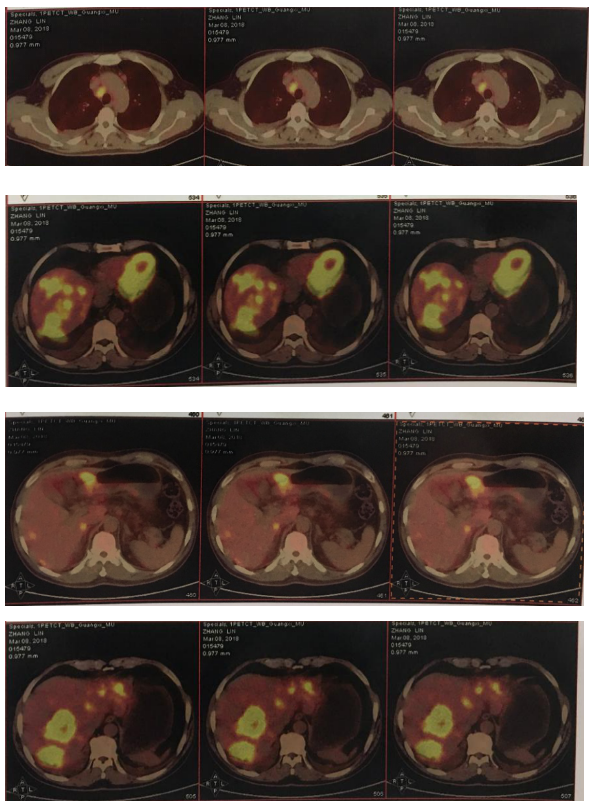

2018-11-19 PET/CT

胃壁代谢稍增高但未见明确的肿物,肝内低代谢结节考虑转移瘤治疗后活性减低,纵膈及右肺门两个淋巴结代谢增高,考虑转移瘤活性尚存、左侧颞骨局部骨质破坏并代谢增高,考虑转移瘤。

经科内讨论,建议患者继续原方案SOX+赫赛汀化疗,左侧颞顶交界区骨质破坏局部射波刀治疗。